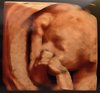

Wg OM 21+1 wg USG 20,4 (wcześniej miałam zawsze starszą o tydzień ale teraz inny lekarz inny sprzęt a może zwolniła troszkę)

Wszystkie narządy prawidłowe

Waga: 407g

Tętno: 148

Łożysko nadal na ścianie przedniej a dzidzia obecnie siedzi miednicowo z główką pod pępkiem :)

Termin porodu wg OM 8 kwiecień, wg pierwszych prenatalnych 3 kwietnia a teraz 11

No i dziewczynka :) trzech lekarzy tak twierdzi więc może się nie mylą